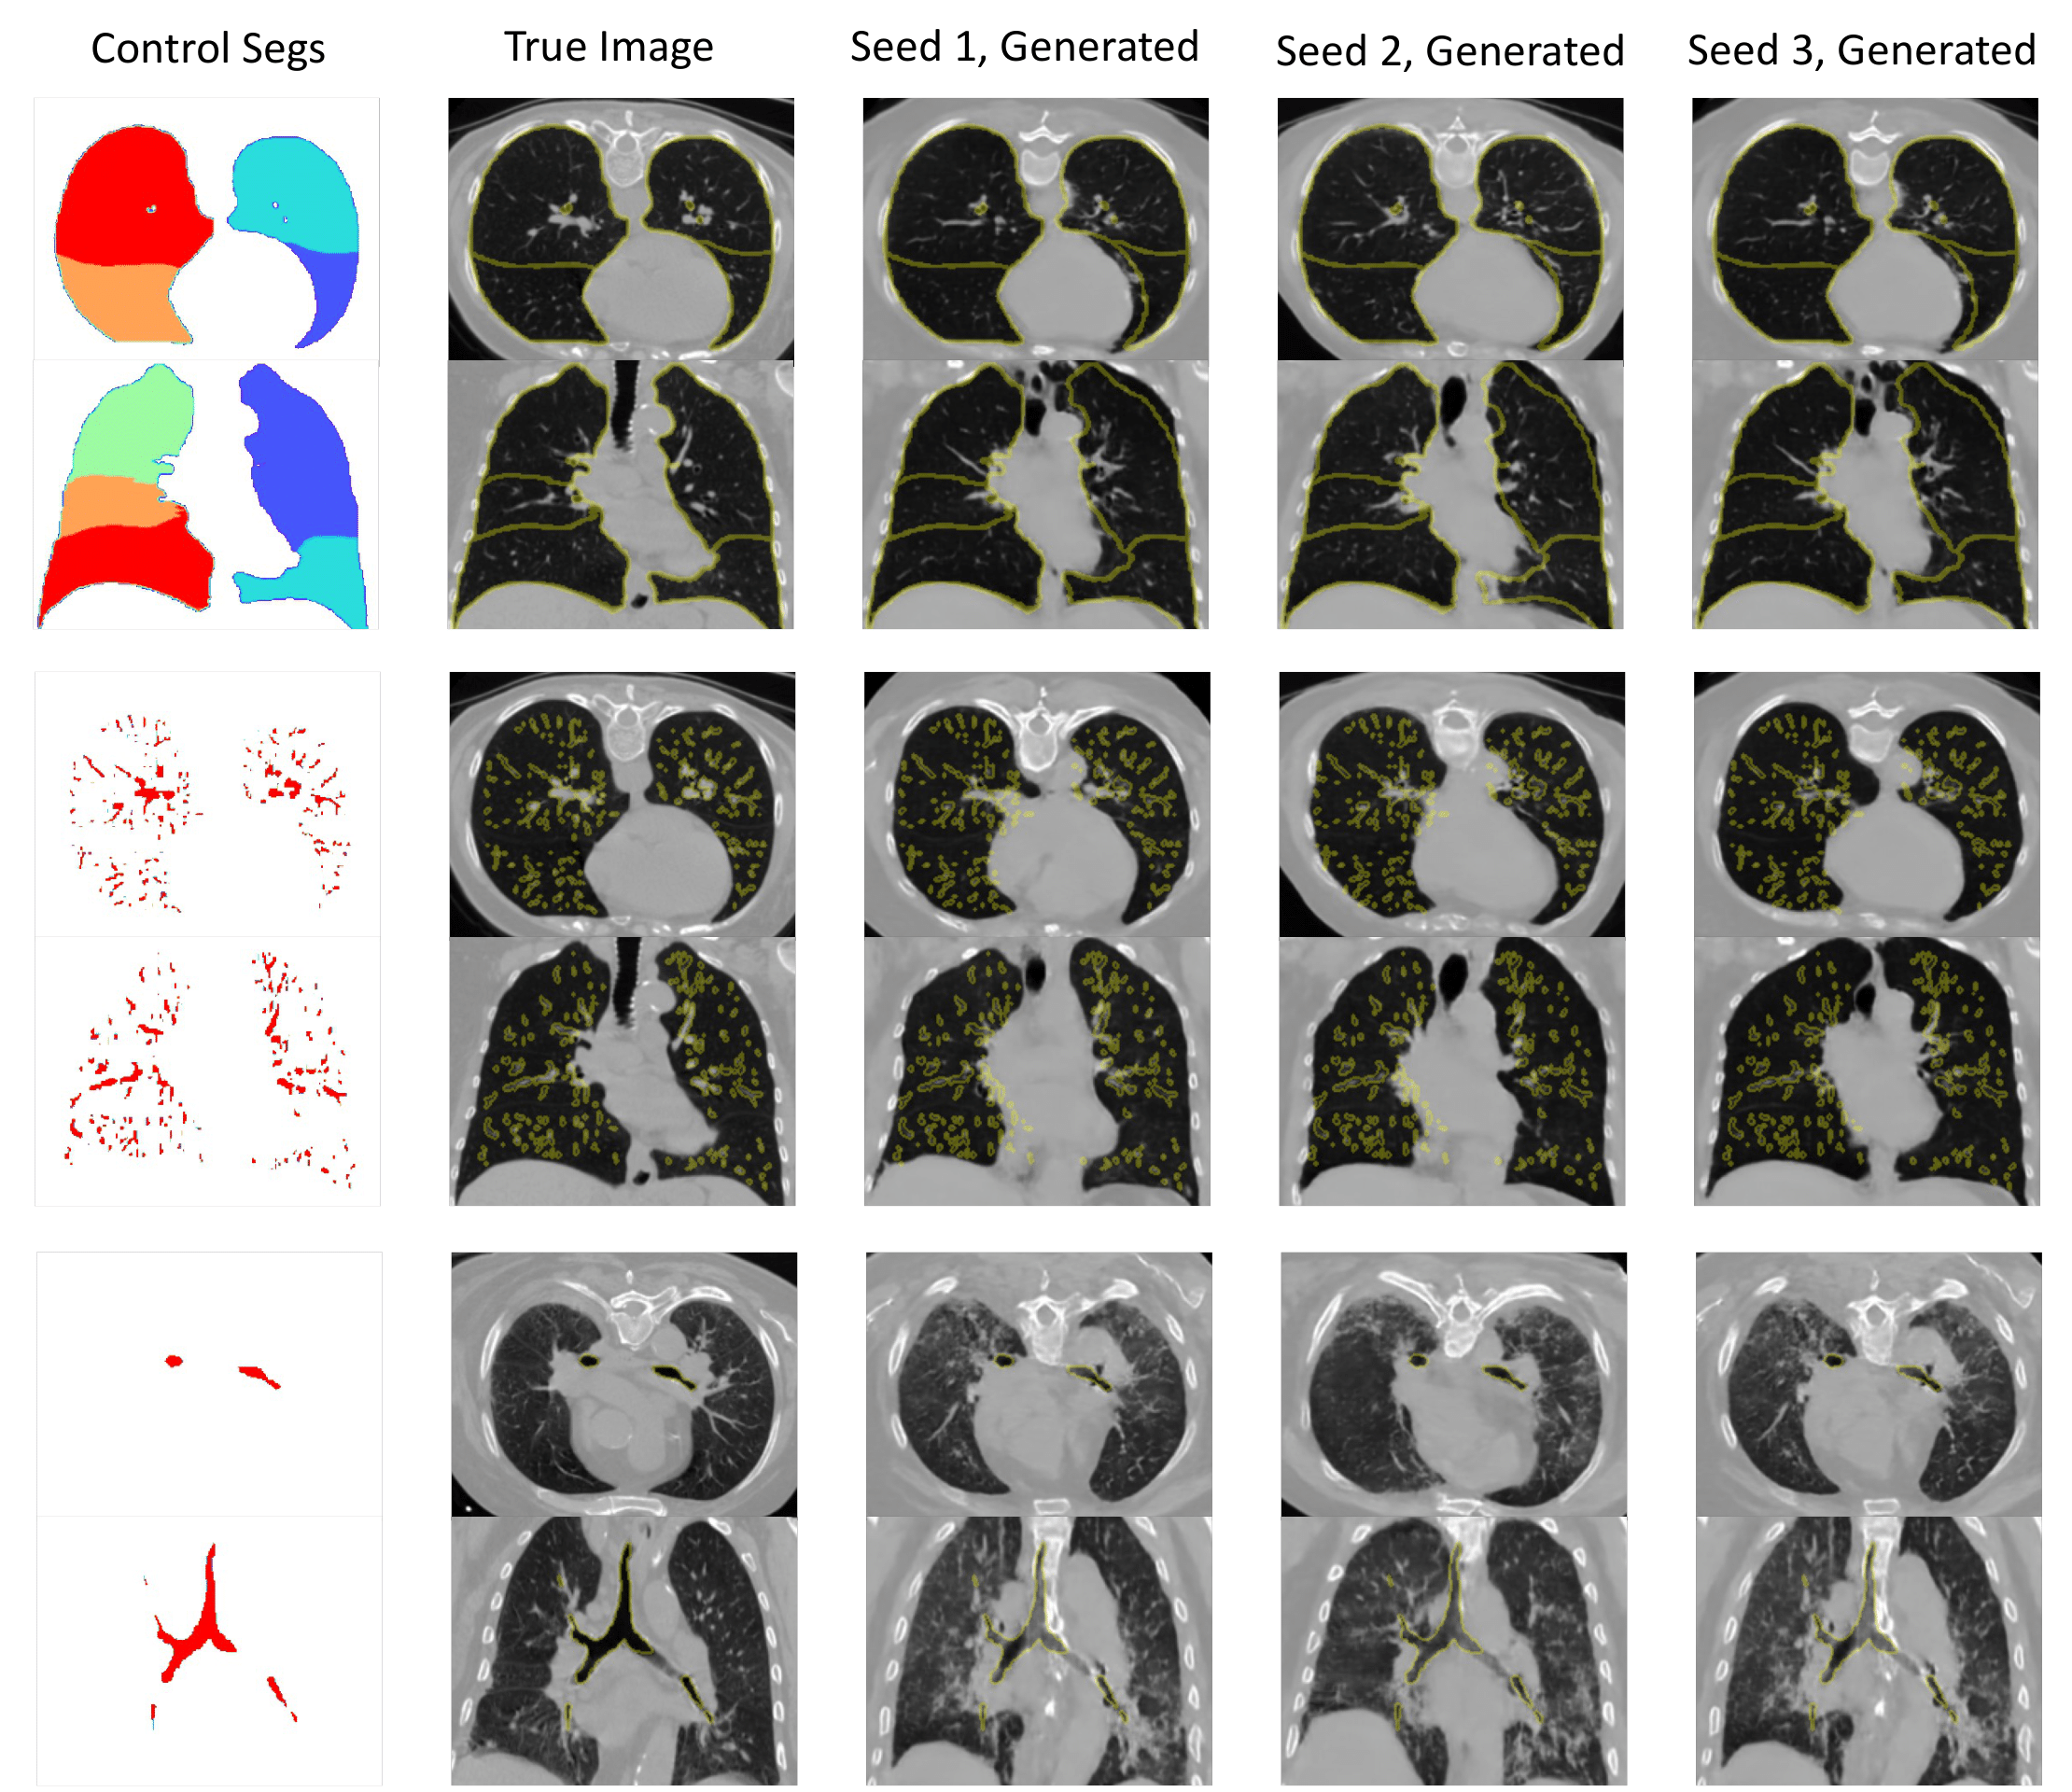

Refer to caption

Figure 6: Controlled volume synthesis via the anatomical priors. The first column shows the anatomical mask used as the condition. The second column shows the corresponding real images. The remaining columns show samples of conditionally generated images. The results show that the generated images can preserve the conditioning anatomical structures.

5.4 Controllable Synthesis via Marginalization of Anatomical Structures

In this section, we explore the application of conditional generation. In this study, we aim to generate data when the anatomical structures are available, such as we can simulate the structures of lobes, airways or vessels. Conditioned on those priors, we are able to provide volumetric CT scans through our model. In Fig 6, we fix the lobes, vessels or the airway in the input channel, respectively, which are segmented from the real data. Then, we generate the lungs with those anatomical structures, which shows great consistency with those anatomical priors and variance for different seeds.